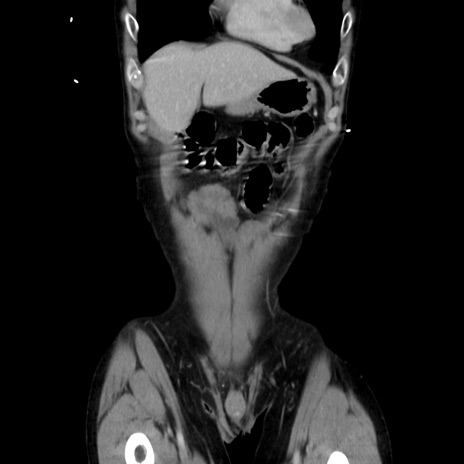

症例37(冠状断像)

【症例】40歳代 男性

【主訴】腹痛

【現病歴】4時間ほど前に電車に乗車中に臍部上より腹痛出現。徐々に増悪し起立困難となり、救急外来受診。生ものは数日食べていない。今朝お雑煮を食べた。

【身体所見】BT 36.8℃、BP 117/84mmHg、HR 91/min、SpO2 97%、苦悶様、腹部:臍上部広範囲圧痛あり、反跳痛±

【データ】WBC 8100、CRP 0.03